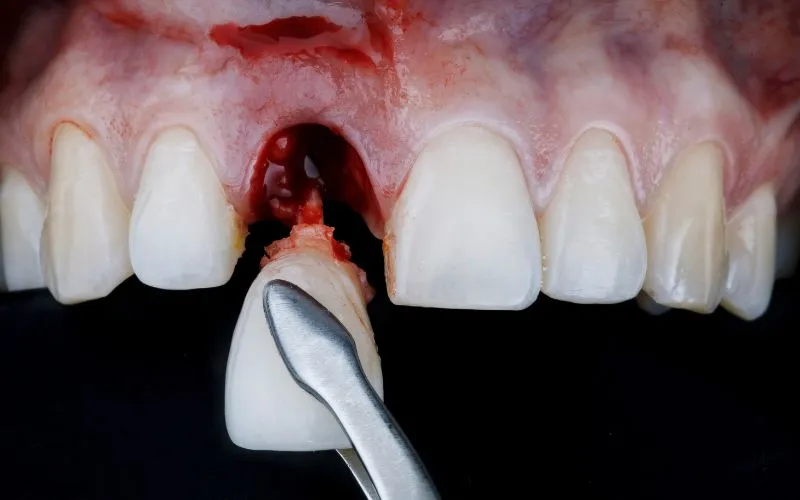

Bezpośrednio po ekstrakcji zęba w miejscu po usuniętym korzeniu rozpoczyna się niezwykle ważny proces tworzenie skrzepu krwi. Ten skrzep, przypominający ciemnoczerwony żel, jest Twoim naturalnym opatrunkiem. Jego głównym zadaniem jest zabezpieczenie rany przed bakteriami z jamy ustnej i stworzenie podłoża dla komórek, które rozpoczną proces odbudowy tkanki. W pierwszych 24-48 godzinach po zabiegu możesz odczuwać ból, który jest reakcją na uraz. Często towarzyszy mu również obrzęk, który zazwyczaj osiąga swoje maksimum w drugim dniu po zabiegu. Niewielkie sączenie się krwi jest również normalne. Pamiętaj, że ból w tym okresie jest najbardziej intensywny, dlatego ważne jest stosowanie zaleconych przez lekarza leków przeciwbólowych.

Między trzecim a siódmym dniem po wyrwaniu zęba powinieneś zauważyć stopniowe zmniejszanie się bólu i obrzęku. To dobry znak, świadczący o tym, że Twoje ciało skutecznie radzi sobie z gojeniem. W tym czasie rozpoczyna się proces ziarninowania tworzenia nowej tkanki łącznej, która powoli zaczyna pokrywać skrzep. Rana zaczyna się zasklepiać od brzegów. Jeśli podczas zabiegu założono szwy, zazwyczaj są one usuwane około 7 dni po ekstrakcji, chyba że były to szwy samorozpuszczalne.